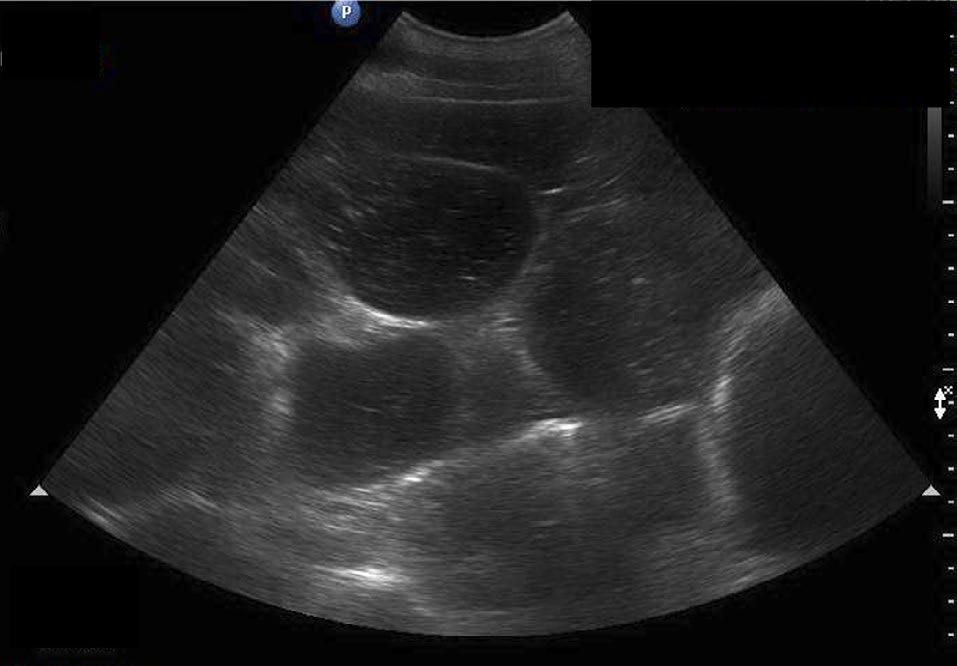

An abdominal ultrasound of the patient was performed using the “fast localised abdominal sonography of horses” (FLASH) approach (Busoni et al., 2011). The stomach was distended with fluid, with the caudal gastric axis extending to the 15th intercostal space. Nasogastric intubation was performed immediately, which liberated spontaneous, malodorous, dark green gastric reflux with a total net volume of 20 L. Continued FLASH examination revealed multiple, distended, amotile loops of small intestine (SI) in all quadrants of the abdomen (Figure 1); these loops measured 6-7 cm in diameter, and all wall thicknesses measured <3mm. There was a moderate increase in anechoic peritoneal fluid. The heart rate reduced to

Figure 1: Distended loops of SI seen in all abdominal quadrants